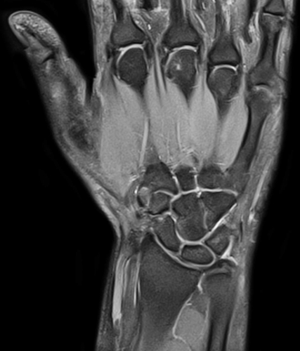

<¼Õ, ¹ß¸ñ MRI>

¼Õ, ¹ß¸ñ ÁúȯÀ̶õ?

¼Õ, ¹ß¸ñÀ» ÁöÅÊÇÏ´Â ÀÎ´ë ¹× ±ÙÀ°µéÀÌ ¿ÜºÎÀÇ Èû ¶Ç´Â Æò¼Ò »ýȰ½À°üÀ¸·Î ÀÎÇÏ¿© ¼Õ»óµÈ °æ¿ì¸¦ À̾߱â ÇÕ´Ï´Ù.